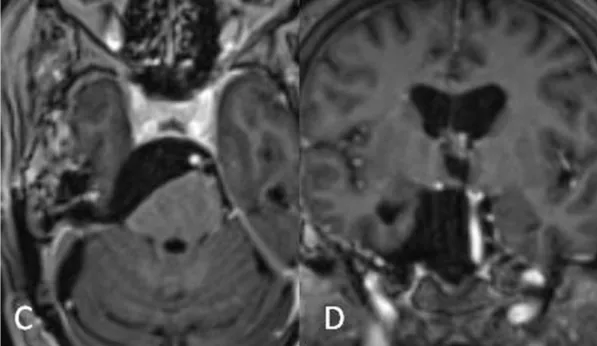

经过周密的术前准备,福教授手术团队为患者实施了颅内肿瘤切除术。手术采用mini-CTPA入路切除肿瘤。在脑干上的附着残体进行了近全切除(NTR)(图C, D)。术后患者未出现神经功能缺损。

术后:C术后轴位和D位冠状位磁共振增强图像显示肿瘤大体切除,神经血管结构有效减压